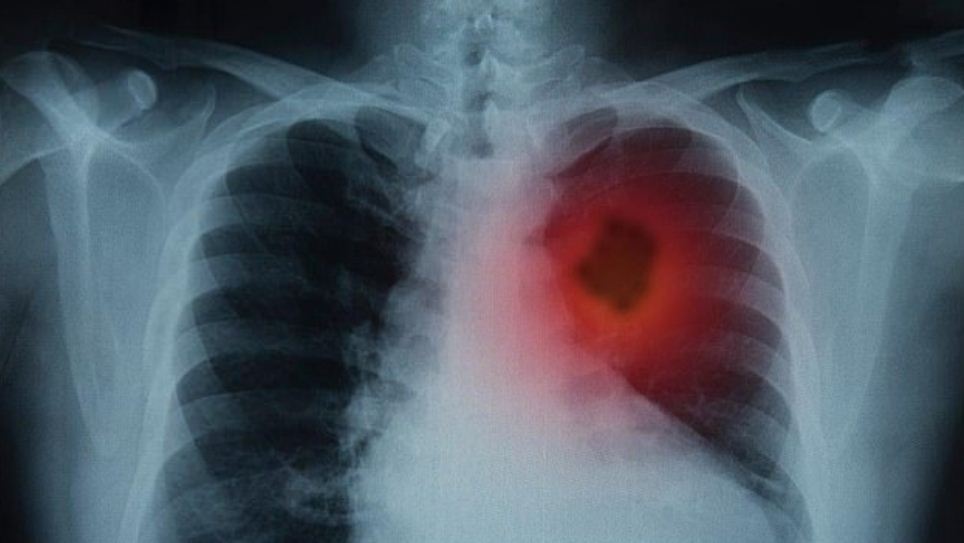

According to Cancer Research UK, the symptoms are pretty common when it comes to certain types of lung cancer with as many as 35% of people with the condition having cancer.